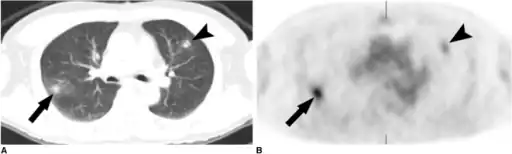

The diagnosis of Loffler's syndrome can be challenging, as the diagnostic criteria can be vague and consistent with a multitude of diseases or conditions. The disease's developmental trajectory is mostly unknown. Upon examination of symptoms, a doctor will likely request a chest x-ray looking for migratory pulmonary infiltrate, and blood testing, to confirm a diagnosis. Symptoms tend to be brief, but can range from mild to severe and include: fever, vomiting, increased respirations or difficulty breathing, cough, wheeze, and rash. Symptoms typically follow an exposure to allergens or certain drugs, and last approximately two weeks.[4]